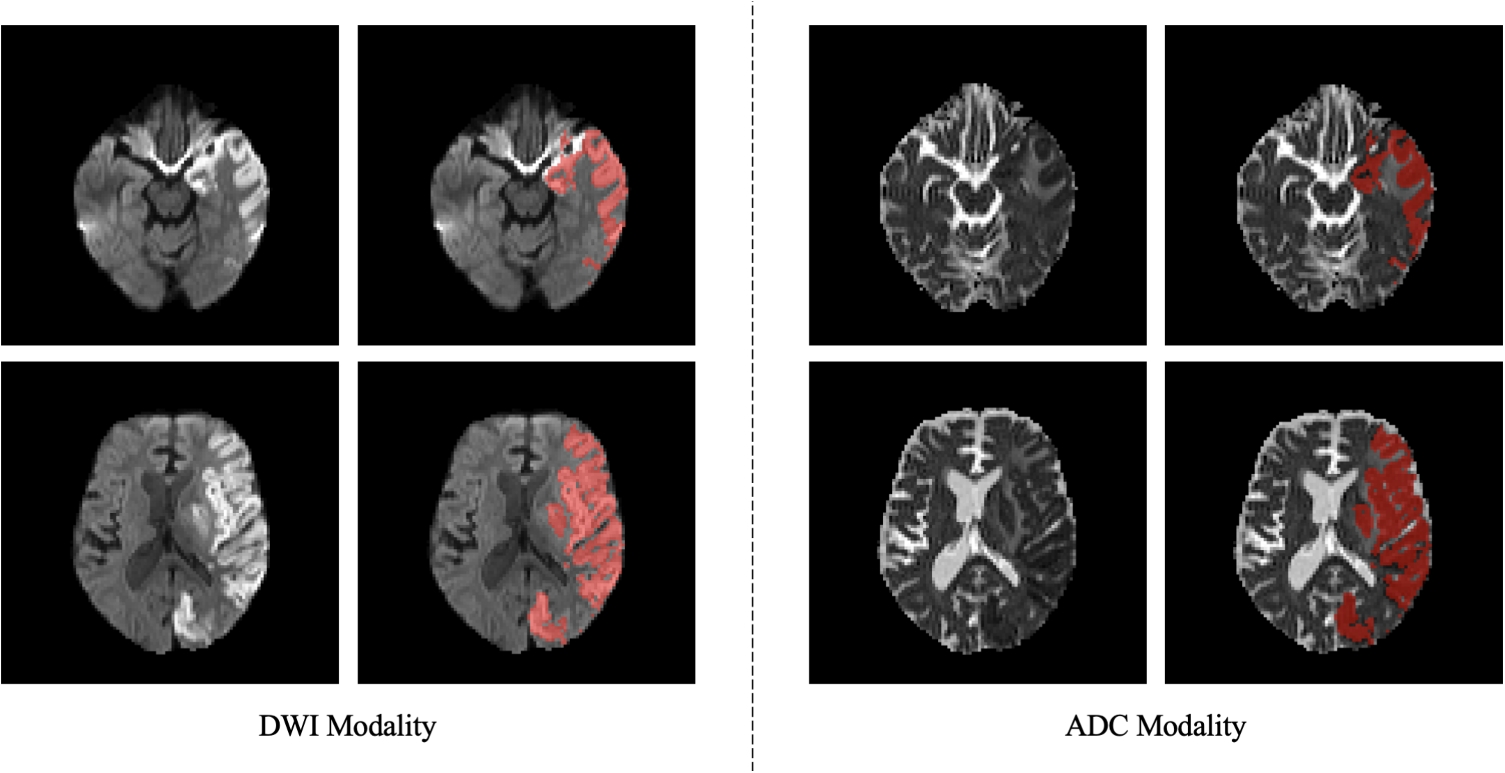

A further comparison with literature methods consists of the glottal area segmentation. The model used for this approach is the same as the one used in the proposed heatmap regression method described in the “Materials and Methods” section. In this case, the model is trained for segmentation using the endoscopic frame and the associated mask. The segmentation mask was constructed from the coordinates of the three keypoints: a triangle was formed by the three keypoints LV, A, and RV to define the glottal region mask, assigning to the pixels inside and outside the triangle the values of 1 and 0, respectively. The model was trained using the Dice (DSC) loss, defined as L = 1 - DSC, where DSC is the Dice similarity coefficient, defined as \(DSC = \frac\), where TP and FP are the true glottal area and background pixels detected as glottal area, respectively, while FN refers to glottal pixels that are segmented as background.

For a fair comparison, the ablation study and the comparison with the literature were performed using the same five-fold cross-validation, training setting, and computational hardware. To evaluate the performance of our framework for VF pose estimation and to compare it with the other tested models, we computed the root mean square error (RMSE) [pixels]. In the case of the heatmap regression model, the RMSE was calculated by comparing the coordinates of the ground-truth keypoints and the predicted coordinates, calculated by identifying the positions of the maximum activation value in the predicted heatmaps. In the case of the glottic segmentation model, the coordinates of the keypoints were obtained from the vertices of the smallest enclosing triangle that contains the predicted segmentation masks. The DSC was also used as a metric to further assess the segmentation model performance. All metrics were computed at the image level, ensuring an independent evaluation of each prediction.

Qualitative results from the comparison of all the tested models on three test samples. The improvements brought by the proposed heatmap regression model are particularly evident in the accurate positioning of the keypoints coordinates, even in more challenging cases, such as reduced glottic opening, or the presence of blur